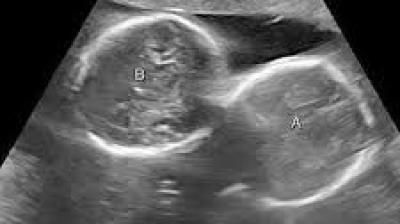

अल्ट्रासाउंड जांच में महिला के गर्भ में दो बच्चों की पुष्टि हुई थी

इंदौर। इंदौर के ESIC अस्पताल से प्रेगनेंसी का एक बेहद चौंकाने वाला मामला सामने आया है. यहां पर एक महिला ने तीन बच्चों को जन्म दिया. इससे भी ज्यादा हैरान...